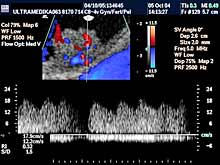

- Broad band-CD (Color-DoppIer) - pruža znatno precizniju procenu

brzine i otpora proticanja krvi u krvnim sudovima, jer je moguće

registrovati različite brzine svih eritrocita. Zbog toga je znatno

preciznija i procena protoka krvi u krvnim sudovima tumora, nego

kod konvencionalne kolor-Doppler tehnike.